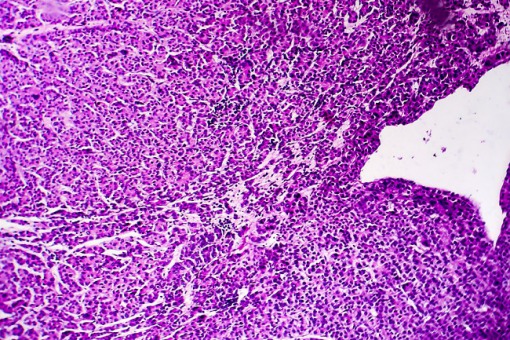

Rak wątrobowokomórkowy (HCC) jest najczęstszym nowotworem na świecie i najczęstszą przyczyną zgonów spowodowanych rakiem. Wraz z postępami dokonanymi w ostatnich latach w diagnostyce i technikach leczenia HCC wskaźniki wczesnej diagnozy guza i długoterminowego przeżycia rosną.